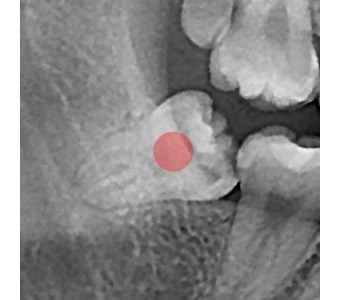

결과로 증명합니다.

국제모아치과의

실제 임상 증례